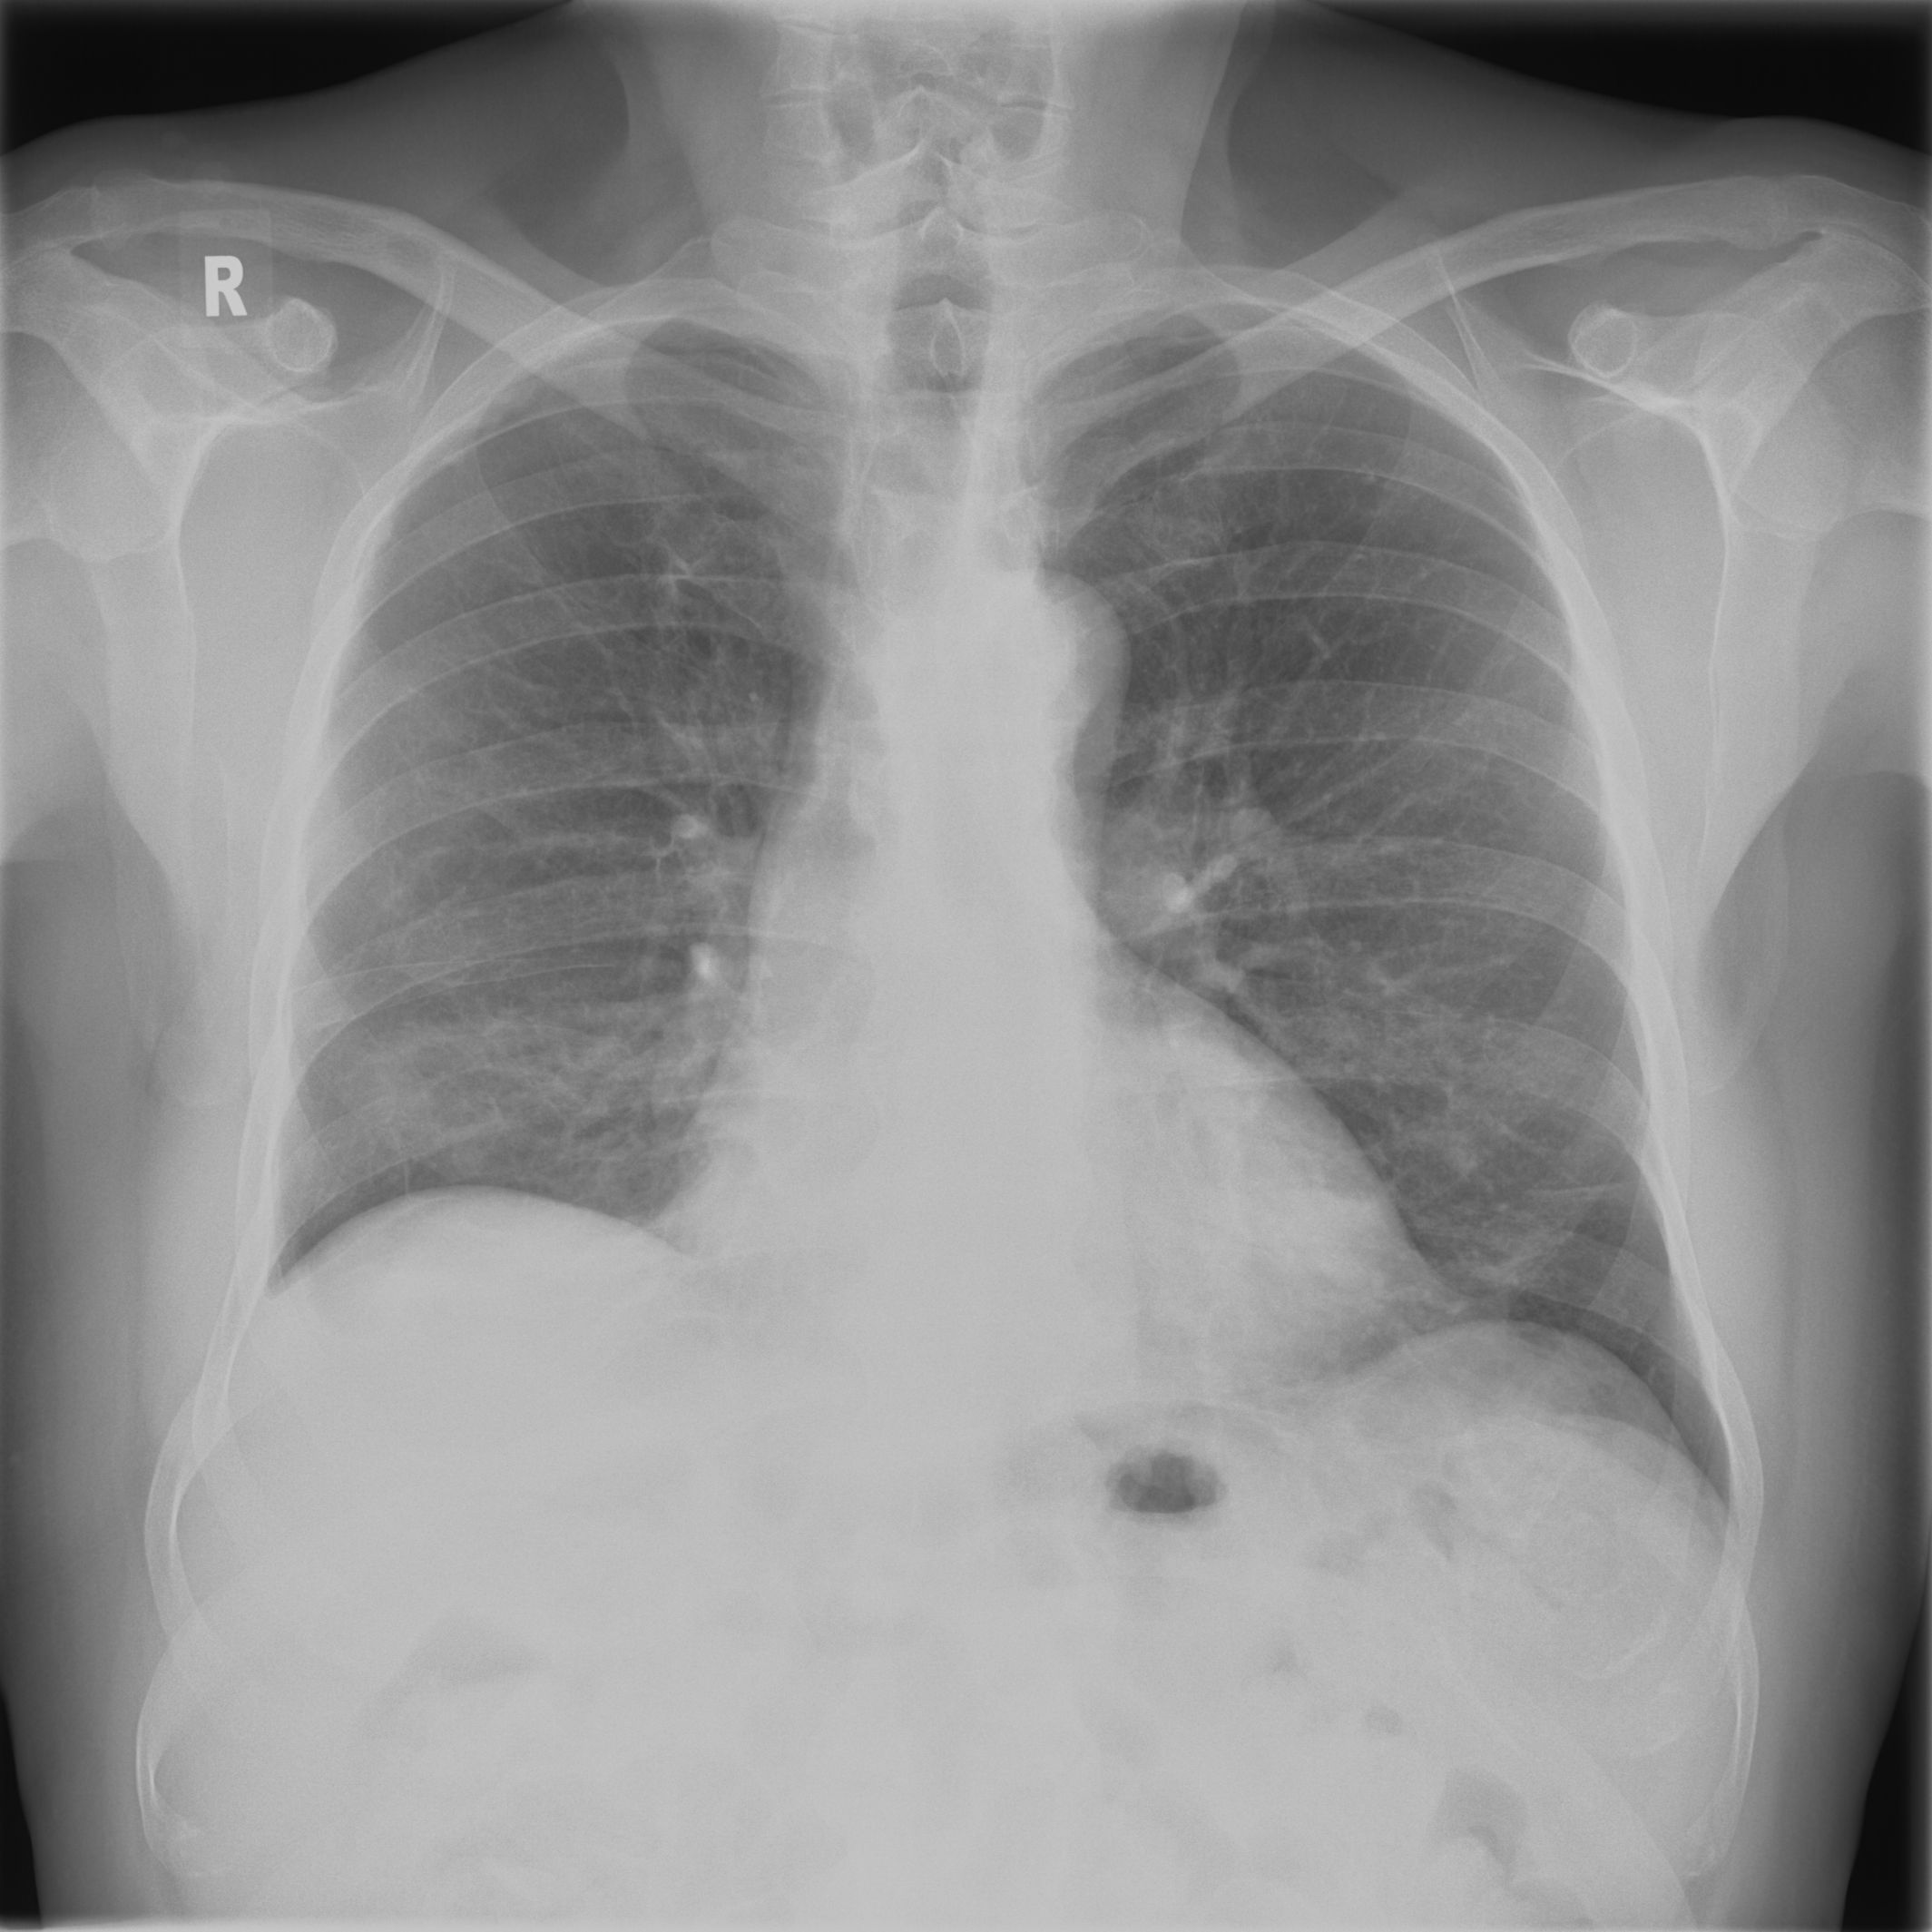

3.3.2 Data

Posteroanterior chest radiographs were acquired on two imaging systems (both Discovery XR656 HD models, GE Healthcare, USA) at Cambridge University Hospitals NHS Trust. Each scanner was being set up in the hospital with different post-processing parameters (chosen by the operating radiologists), which are used here as reference images, see Figure 7 and 8(a). Additional images, serving as real-life examples of lower quality, were produced for each radiographic exposure using multiple different post-processing settings. The post-processing was applied in the hospital directly on the scanner itself by adjusting parameters in the provided framework.

Refer to caption

(a) Reference

(b) (21.1, 0.90, 0.11)

(c) (19.5, 0.88, 0.16)

Figure 7: Chest X-Ray scans with different kinds of post-processing; (a) serves as reference and (b) is wrongly judged as better visualization by PSNR/SSIM/LPIPS.

(b) (22.8, 0.97, 0.08)

(c) (21.2, 0.96, 0.07)

Figure 8: Chest X-Ray scans with different kinds of post-processing; (a) serves as reference, (b) is wrongly judged as better visualization by PSNR and SSIM, LPIPS gives a slightly worse evaluation for (b).

In Figure 7, contrast deviation and edge enhancement were reduced in (b), but increased in (c), the noise reduction algorithm was removed in both. The brightness was increased in both images but more so in (c) and low-contrast enhancement was removed in (b). The result is that (b) has relatively low contrast in the lungs compared to the reference (a) and radiograph (c). In Figure 8, edge enhancement has been dramatically increased in (b), whilst the contrast deviation and tissue contrast have been reduced. In (c), the brightness, tissue contrast and edge enhancement have been slightly increased. Consequently, (b) provides low contrast in the lungs with excessively prominent lung markings and vasculature which make it harder to detect abnormalities such as a pneumonia.

FR-IQA mismatches

In Figure 7 and 8 we apply the standard FR-IQA metrics to the images with diverging quality. Although it is visually obvious that image (b) has lower visual quality, it is judged wrongly as the better image by all measures in the first example Figure 7, and the results in (b) and (c) of the second example Figure 8 are quite close, where PSNR and SSIM are also providing the wrong order. This indicates that the tested standard FR metrics are not suitable to evaluate the quality of data sets with X-Ray images that have large variations regarding contrast, luminance and sharpness.